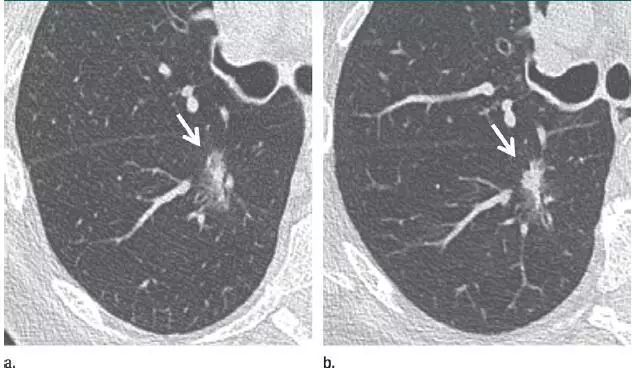

6、毛刺状结节

图片

图 6 左肺上叶层厚 1 mm 的 CT 横断面图像,显示一个可疑的实性毛刺状结节(箭头)。手术证实为浸润性腺癌。